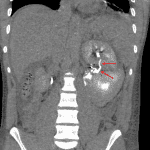

- Large left renal laceration with absent enhancement of the lower half of the left kidney and large perinephric hematoma. Areas of contrast density in the perinephric hematoma which become larger on delayed phase images

- Filling defects within opacified upper and interpolar left renal calyces

- Small linear hypodensities in the inferior tip of the spleen

- Retroperitoneal hemorrhage surrounds the pancreas without discrete pancreatic laceration

- Renal laceration

High-grade left renal laceration with devascularization of the inferior half of the kidney and large perinephric hematoma with areas of active extravasation. Filling defects in the left renal collecting system could represent debris or blood clot. Given hilar involvement, a CT urogram should be considered to assess for urine leak.

Grade I laceration along the inferior margin of the spleen.

Retroperitoneal hemorrhage surrounds the pancreas. Although no discrete pancreatic laceration is seen, an occult injury is not excluded.